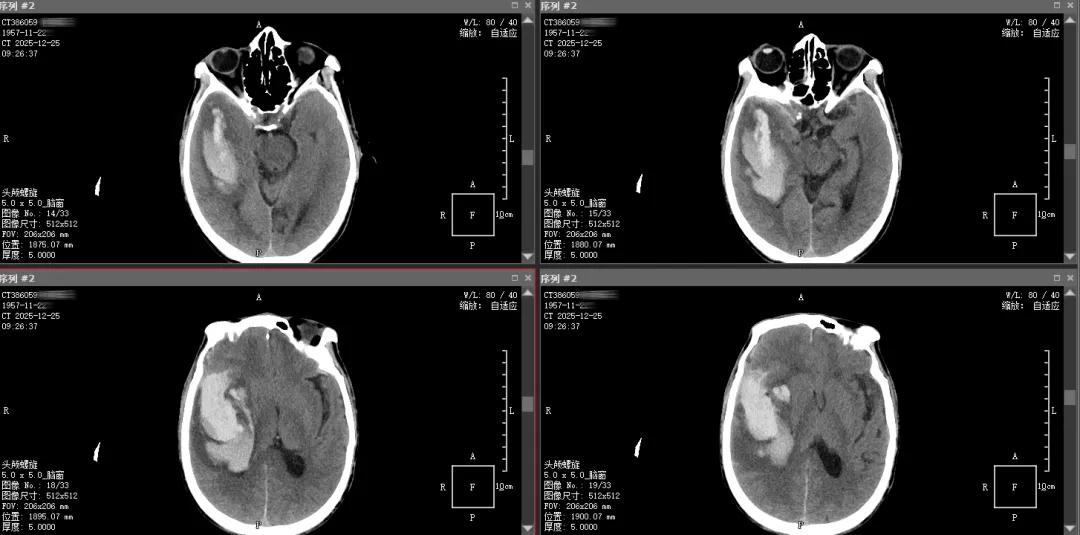

▲术后12天复查头颅CT影像图